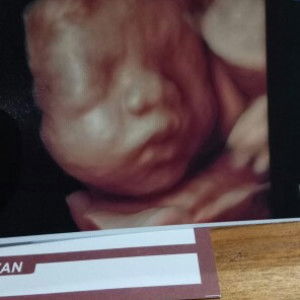

perut bergetar, usia hamil 9wks

Moms, mau tanya dong.. usia 9wks udah bisa usg biasa, kan? Perutku dalemnya ada yang nendang² gitu sekarang, terus ada yang gerak² getar² gitu.. normal ga sih di usia kandungan 9wks?? mau usg masih nunggu jadwal pekan depan di bidannya..